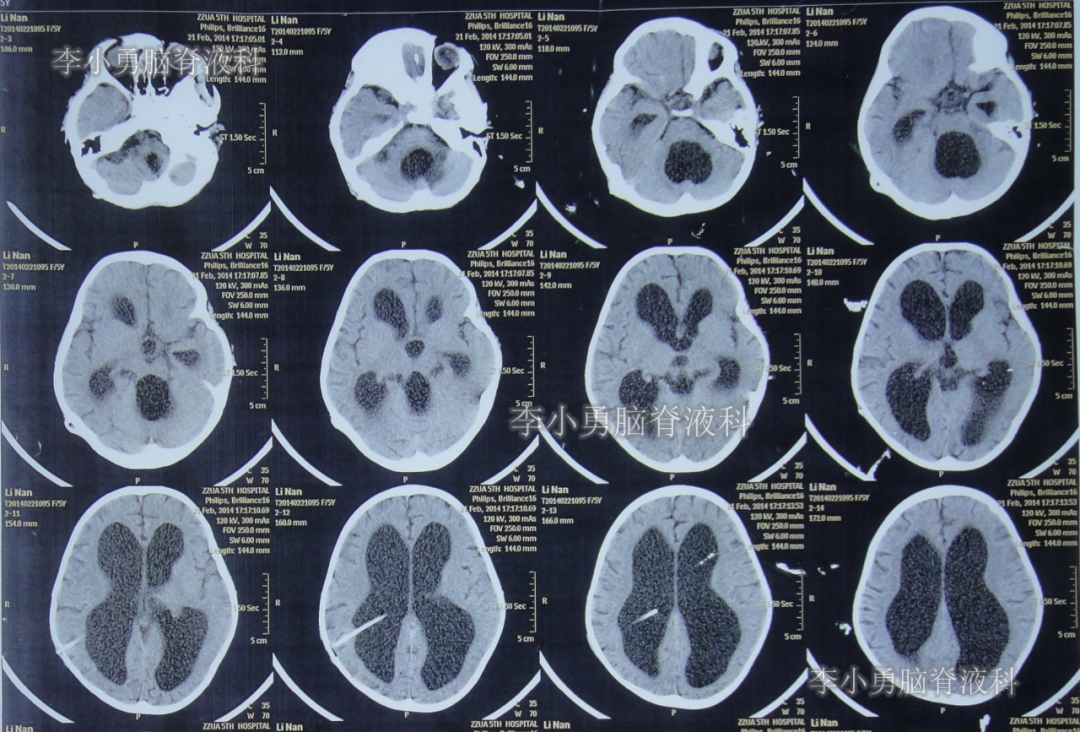

于2014年2月11日即脑室心房分流术后第122天时,患儿突然再次出现头痛和呕吐的症状,立即又第3次返回河南省郑州市某三甲医院神经外科住院治疗,当天查头颅CT显示脑室系统再度扩张严重(图-2)。

图-2:2014年2月11日头颅CT

第3次住院后第10天即2014年2月21日,复查头颅CT显示脑室系统仍扩张严重(图-3)。

图-3:2014年2月21日头颅CT